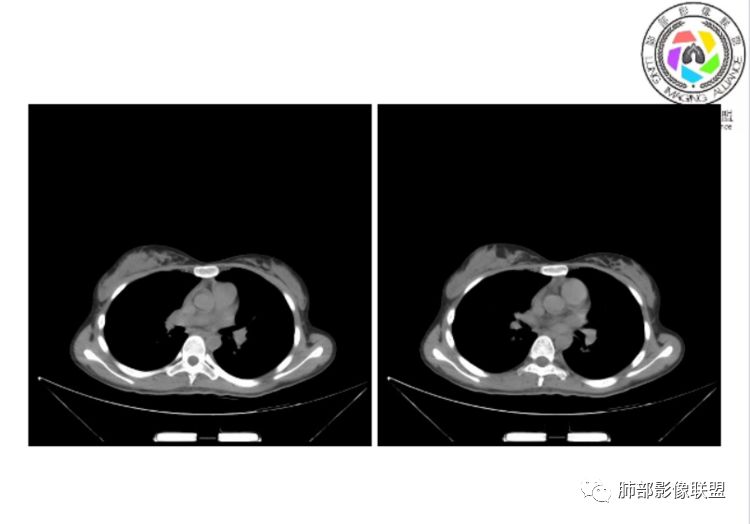

小微:右肺下叶斑片状密度增高影,抗炎治疗6天后复查,双肺下叶出现斑片状密度增高影,排除炎性病变,D2聚体特别高,考虑肺栓塞,肺梗死,建议增强扫描。王开金江津中心医院呼吸科:@岳微-辽宁PLA234医院放射科?支持,患者年轻女性,胸痛主诉,使用雌激素,高危人群,心率快,d二聚体升高,右下叶斑片加肺动脉明显增宽,抗感染无效,要考虑PTE,建议肺动脉ctpa。傅昌瑜:19岁,女性,右侧胸痛2天,发热以中度热为主,D—二聚体升高,肺动脉主干增宽,病灶位于胸膜下,抗感染后增多,近来有服用炔雌醇环丙孕酮片2周期史,诊断:肺栓塞,下一步完善肺CTPA检查。阿仙奴:青年女性,急性起病,胸痛入院,月经不调史,目前服用孕酮片。流感抗体阳性,d二聚体升高,无低氧血症。右肺下叶基底段胸膜下磨玻璃样改变,肺动脉增宽,治疗过程出现发热,复查左下叶胸膜下新发病灶。考虑:肺栓塞(服用孕酮相关)?奔跑的37°Doctor(陆喜红 ) :年轻女性,胸痛 急性病程,有服用雌激素避孕药史(是否有血液循环的改变,高凝状态),实验室D二聚体很高(也是提示血液高凝状态) ,第一次CT,右下肺胸膜下斑片状密度增高模糊影,肺动脉形态密度未见明显异常,抗炎后复查,肺动脉干及其分支,感觉增粗了一点,局部形态有点饱满,双下肺胸膜下片状影增多,锁定肺动脉栓塞应该不会错,建议CTA检查飞鹰行动:青年人,女性,右肺下叶斑片状密度增高影,抗炎治疗6天后复查无好转,,双肺下叶出现斑片磨玻璃影,主肺动脉增粗,结合患者服用的药物和D2聚体特别高,考虑肺栓塞,建议CTA。李:口服避孕药,有危险因素,肺动脉较主动脉增宽,D二聚体增高,胸膜下片状影,考虑肺栓塞;@晨义工张帅,医附属潞河医院呼吸?是否痰中带血很关键,不知有没有张帅:患者入院后第七天出现痰中带血风之子:病程中有发热,D—二聚体升高,肺动脉主干增宽,病灶分布于胸膜下,抗感染后增多,结合服药史诊断:肺栓塞,建议CTPA检查。不支持的地方是没有低氧血症,不明白为什么第二次复查ct双侧乳腺不对称,按理乳腺炎多见于哺乳期张帅:大家方向都在考虑肺栓塞:我提问两个问题:1 周围毛玻璃怎么回事?2左下肺小叶间隔增宽怎么回事?笨丫头:周围的磨玻璃应该考虑是肺梗死后出血渗出,同时合并机化性炎症小叶间隔增宽,我考虑应该是梗死后炎性渗出wonderful:我不支持肺栓塞 不能解释发热原因

CTPA(CT断层肺血管造影)是对疑似PE患者肺血管系统成像的首选方法,可直观判断肺栓塞的程度和形态,以及累及部位及范围,可以从直接或间接征象进行诊断,但是对亚段及远段肺动脉血栓敏感性较差,联合肺动脉造影可以使PE诊断敏感性增强。

CTPA直接征象:

1、肺动脉中央部分充盈缺损

2、偏心性或附壁充盈缺损

3、骑跨型血栓

4、完全型充盈缺损,动脉截断,远端动脉分支内无造影剂

CT平扫及间接征象:

1、一个或多个胸膜下斑片高密度影(梗死、出血、肺不张、肺水肿、炎性渗出),典型为胸膜下楔形影 ,尖端指向肺门

2、肺动脉高压(中心肺动脉扩张),有时可见肺动脉区高密度影。

3.影像:病变胸膜下多发斑片影,提示与血管有关,早期病变为渗出,应该是早期的炎性渗出,病灶抗感染治疗后实变区增多、变大,临床症状又出现咯血,CT上应该合并了肺泡出血、梗死、肺不张及肺水肿;